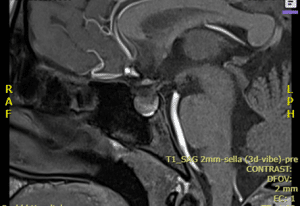

On the first day of admission, aside from basic investigation, the following was done. Lumbar puncture was unremarkable, and Meningitis/Encephalitis (ME) Panel (Multiplex PCR) detected no organisms. CT without contrast revealed no acute intracranial abnormality. On the second day, an MRI brain with contrast (MRA) was ordered, which showed a pituitary gland height of about 09-10 mm, with findings suggesting hemorrhage within the gland. On the third day of admission, MRI of the sella T1 sequence showed a mild increase in the size of the pituitary gland with heterogeneous enhancement and curvilinear hyperintensity in the floor of the sella, suggesting hemorrhage within the gland. Areas of infarct, however, were not seen (image 1).

Figure 1: MRI of the sella T1 sequence showed a mild increase in the size of the pituitary gland with heterogeneous enhancement and curvilinear hyperintensity in floor of sella, suggesting hemorrhage within the gland. However, areas of infarct were not seen.